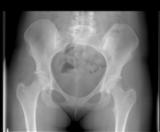

Active axial spondyloarthritis with advanced structural lesions